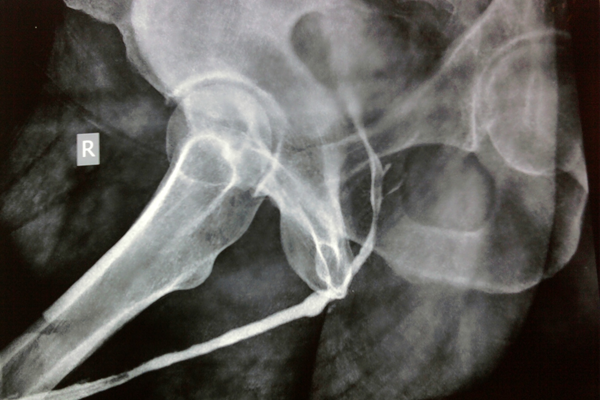

Stricture Urethra In 35 Yr Young Gentleman With H/O Major Abdominal Surgery And H/O Prolonged Urethral Catheterization. Underwent Multiple EIU And Urethral Dilation Presented With Voiding Difficulty. Fig: Ascending Urethrogram Showing Pan-Urethral Stricture

Mr Shyam Meena (name changed) 29 yr a young boy employed in a shipping company. He was trapped between a metallic door in a submarine and sustained a crush fracture of the pelvis. He developed retention of urine with urethral bleeding. Underwent emergency surgery for pelvic brim (pelvic girdle) fixation and suprapubic catheterization. He was not able to pass urine through the urethra because of complete disruption at the level of the prostatomembranous urethra. He approached me and then after evaluation, the diagnosis of PFUDD (pelvic fracture urethral distraction defect) was made. He underwent a successful urethroplasty.